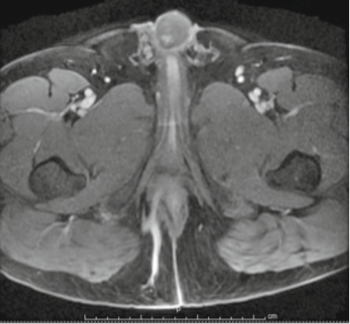

- A MRI fistulogram sometimes is mandatory to delineate the fistula tract type, its relation to the anal sphincters and any branching or deep abscesses. A simple blood test of ‘serum creatinine’ is a must before going for contrast MRI examination.

CONTRAST MRI SCAN SHOWING FISTULA TRACT (BLUE ARROW)